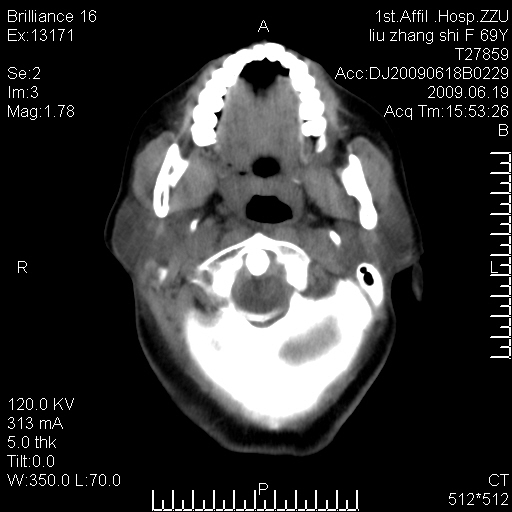

标题: CT26782:女,69岁,颈部占位,3天后公布病理结果。

【病理证实系列】女,69岁,颈部占位,有病理结果,3天后公布。(由于病例时间较久,临床资料不全,请网友见谅)本系列将有几百种常见、少见及罕见病例,均经病理证实。病例资料来自郑州大学第一附属医院。与网友共享,本人有空就发。

支持甲状腺癌广泛侵及周围结构并颈部淋巴结转移。

病理结果:颈部非霍奇金淋巴瘤。